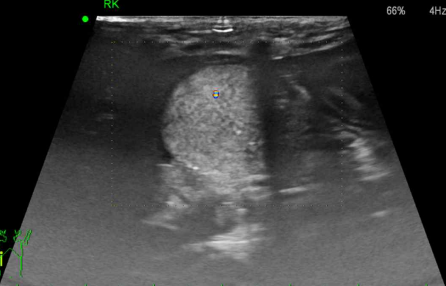

- ์ด์ํ ๊ฒ์ฌ

ํผ์ง, ์์ง ๊ฒฝ๊ณ๊ฐ ์์, hyperechoic